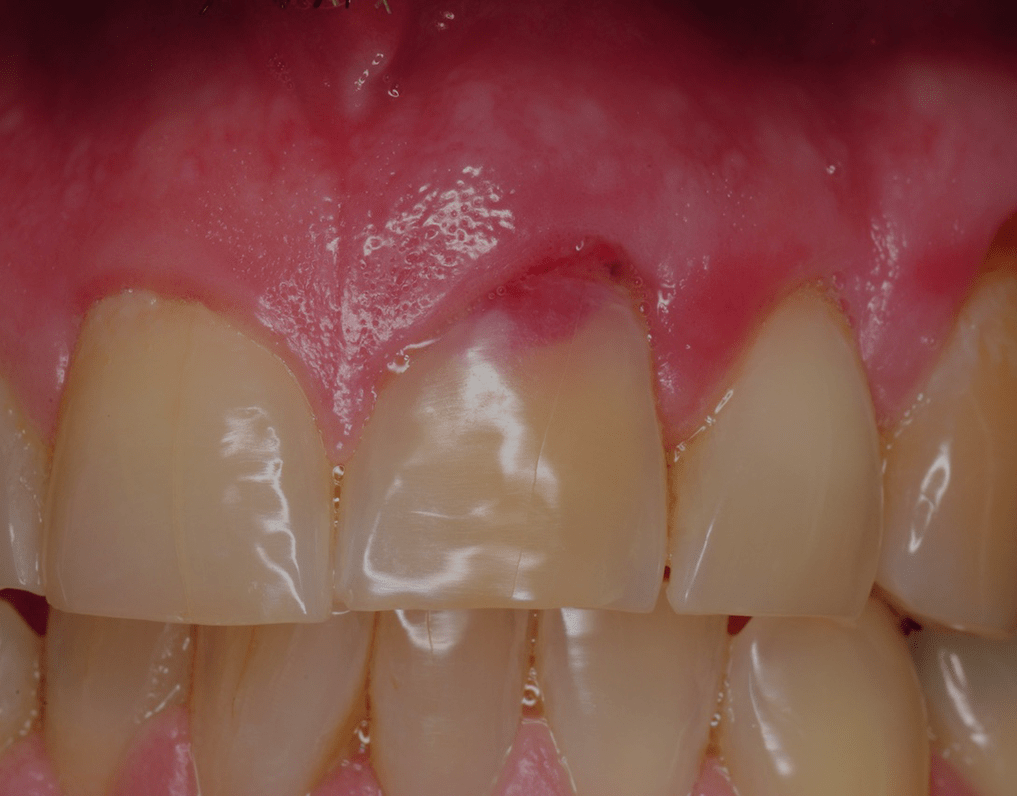

Tooth resorption. A/B) Clinical photograph and radiograph of maxillary... Download Scientific

From www.researchgate.net

Tooth resorption. A/B) Clinical photograph and radiograph of maxillary... Download Scientific Is Tooth Resorption Dangerous Bone cells or the presence of other teeth destroy. tooth resorption can lead to infections, crooked teeth, tooth loss, and other dental problems that can cause lasting damage to your. when root resorption happens outside of losing baby teeth, it’s likely due to tooth nerve or gum infection, tooth. tooth resorption is when the tooth structure is. Is Tooth Resorption Dangerous.